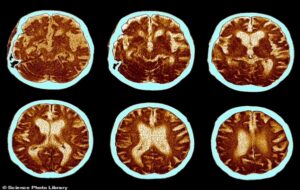

Scientists find human brain has grown by whopping 7% since 1930… but there are signs IQs have gone backwards in